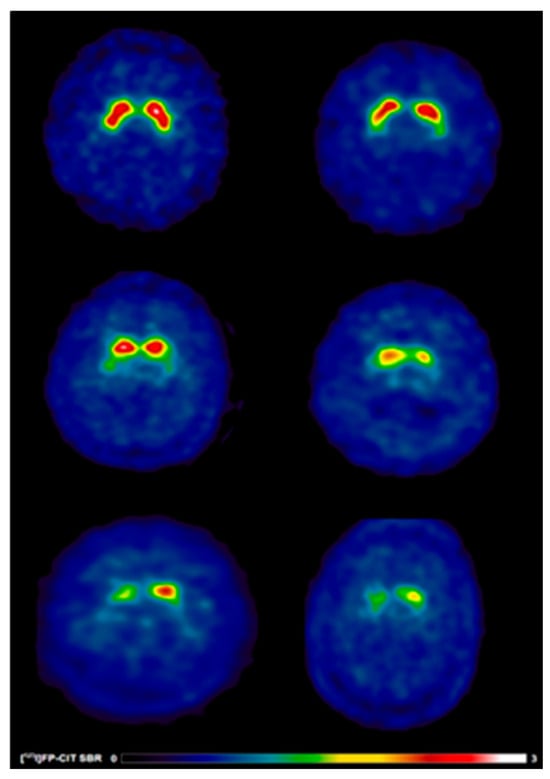

[123I]FP-CIT SBR Values

[123I]FP-CIT SBR

| [123I]FP-CIT SBR | |||

| contralateral_caudate [mean (±SD)] | 1.71 (±0.5) | 1.88 (±0.5) | 0.002 |

| ipsilateral_caudate [mean (±SD)] | 1.97 (±0.5) | 2.24 (±0.5) | <0.001 |

| mean_caudate [mean (±SD)] | 1.84 (±1.8) | 2.06 (±0.5) | <0.001 |

| contralateral _putamen [mean (±SD)] | 0.63 (±0.2) | 0.72 (±0.2) | <0.001 |

| ipsilateral _putamen [mean (±SD)] | 0.83 (±0.2) | 1.03 (±0.3) | <0.001 |

| mean_putamen [mean (±SD)] | 0.73 (±0.2) | 0.87 (±0.2) | <0.001 |

| contralateral _striatum [mean (±SD)] | 2.34 (±0.6) | 2.60 (±0.7) | <0.001 |

| ipsilateral _striatum [mean (±SD)] | 2.81 (±0.8) | 3.27 (±0.8) | <0.001 |

| mean_striatum [mean (±SD)] | 1.29 (±0.3) | 1.46 (±0.3) | <0.001 |

| [123I]FP-CIT SBR * | |||

| contralateral_caudate [mean (±SD)] | 1.39 (±0.4) | 1.58 (±0.4) a | 0.02 |

| ipsilateral_caudate [mean (±SD)] | 1.67 (±0.5) | 1.88 (±0.5) a | 0.02 |

| mean_caudate [mean (±SD)] | 1.53 (±0.4) | 1.73 (±0.4) a | 0.01 |

| contralateral _putamen [mean (±SD)] | 0.51 (±0.1) | 0.60 (±0.1) a | 0.003 |

| ipsilateral _putamen [mean (±SD)] | 0.66 (±0.2) | 0.78 (±0.2) a | 0.008 |

| mean_putamen [mean (±SD)] | 0.58 (±0.1) | 0.69 (±0.1) a | 0.002 |

| contralateral _striatum [mean (±SD)] | 1.90 (±0.5) | 2.18 (±0.6) a | 0.008 |

| ipsilateral _striatum [mean (±SD)] | 2.33 (±0.7) | 2.66 (±0.7) a | 0.01 |

| mean_striatum [mean (±SD)] | 1.06 (±0.3) | 1.21 (±0.3 ) a | 0.007 |